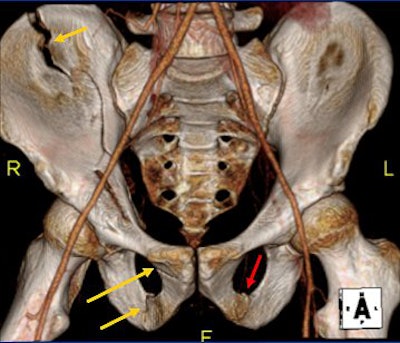

![]() |

| Surface 3D volume-rendered CT of AP pelvis. Right anterior column fracture is well-demonstrated on reconstructed image from trauma CT. The left pubic rami fracture is more subtle than on translucent image. |